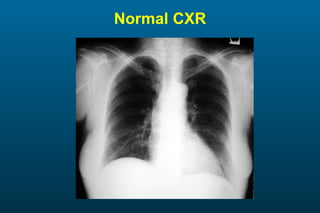

1) The posterior-anterior (PA) view is the standard and most reliable technique for a chest x-ray. It allows detection of air under the diaphragm. 2) A lateral view helps localize infiltrates and evaluate the cardiomediastinal silhouette, effusions, and left atrial dilation. 3) An anterior-posterior (AP) view is used when a patient is too ill to be transported, but image quality is poorer and structures may appear enlarged compared to a PA view.